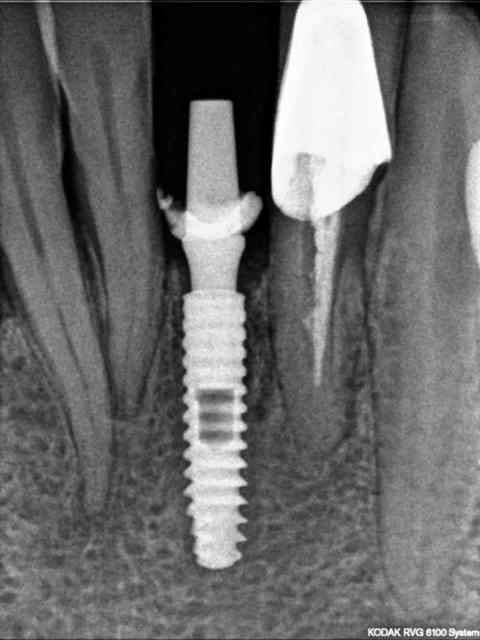

rx à j=0 et j+4 mois

ce qui est surprenant , c'est la présence d'os au niveau du col.